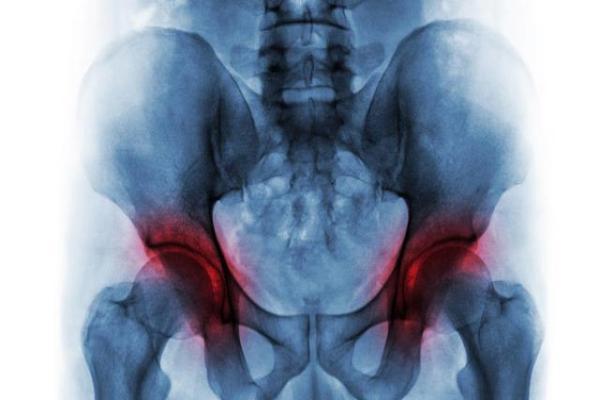

置换术是不少股骨头坏死患者在治疗疾病的时候会选择使用的一种治病方法,有的患者会觉得置换简单,而且比较快,不用再去承受坏死股骨头带来的痛苦折磨。然而对于股骨头坏死是否能够从根本上得到有效治疗并没有关注,这也是造成目前不少股骨头坏死手术患者术后疾病复发的一个主要原因。那股骨头坏死置换对身体有什么影响吗?

股骨头置换对骨头的影响

股骨头置换的弊端1、股骨头坏死置换术的费用比较高,痛苦也非常的大,容易发生感染,导致神经损伤、脱位、假肢下沉,摆动断裂等并发症的出现;